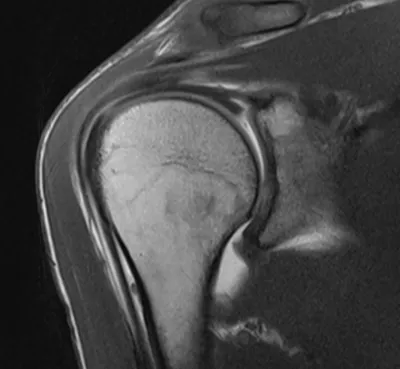

9 imagesPosterior glenoid labral tear